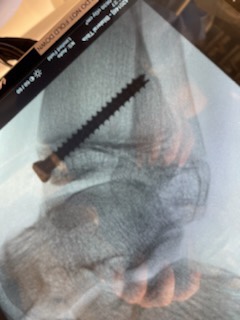

X-rays taken. Doctor comes in, asks her where it hurts, she points, he says “yep, that’s where your fibula is fractured.” I yell “No!” Sporty starts tearing up and cries (remember she didn’t cry when it actually broke but at the thought of missing tournaments, tears) “But I have softball tournaments.” Cast for 4 weeks, though she negotiated checking at 3 weeks since it is a minor fracture and since she’ll be missing her overnight tournament which she was so excited about (me not so much!), he’s going to try to clear her for our tournament in California in July. So we got our first non-Clubfoot cast, we got our first Arizona cast, and somehow we made someone mad enough to make a cast happen in June/July in Arizona. The screw is still in place, in fact, the screw prevented her tibia from breaking so it actually made the fracture less severe than it would have been if the screw was not there.

The good news is, because he got images of her right foot he was able to do a preliminary measurement and so far we have gotten 2 degrees improvement in her right foot in about 2 months. So it looks like the guided growth surgery is working even though I die a little bit inside every time I see her walking on her toes.

We got there and checked in and Sporty was barely in her super fashionable robe (she legit hates the paper shorts and robes) and they were ready to take her in an hour early. Good thing I cut off that third apple juice this morning as we were leaving for the hospital. 😅. She did great, they put an IV in her right away before any meds and she had little to no anxiety about today. They didn’t give her anything until they were about to wheel her back. The procedure lasted about an hour and then they brought me back to meet with the doctor while they got her settled in recovery. He was very happy with how things went! He felt like we were going to have success with this choice and didn’t even feel like lengthening the Achilles would have helped as her talus bone is raised and that is restricting her movement and not her Achilles. Can we get a “what what” for mommy gut!?! So the screws are in there, he felt screws would give a lower profile and make her more comfortable with shoes and such (and doesn’t change the outcome) and then we don’t have to rush to take them out because they won’t be bothering her. We can get 2-15 degrees, hoping for closer the 15 degrees and 2 would not be enough to call it successful. We should start seeing results in 9 months.

Today we met with a local orthopedic surgeon that was referred to us by the doctor in Salt Lake City. They took a TON of x-rays, I think he got more images of her feet today than they have her entire Clubfoot existence. He even watched her run. Her walk gait is good. Her run gait is better, no shock there, she was made to run after all. He said her feet actually look great for clubfoot feet. After his examination the doctor agreed that guided growth was a great option for Sporty. He did say that a tendon lengthening can’t be written off quite yet. It’s not the right route for her right now but we need to keep it in mind for the future. As of right now he thinks we’ll have success with guided growth as she has over a year of growth left on her growth plate in her ankles. He’s done 4 of these, it’s not common in the US, but the 4 he’s done have been successful. And there’s really nothing to lose by trying this. It’s so minimally invasive that if it doesn’t work, it doesn’t change anything, they just take out the screws.

The x-rays show that Sporty’s growth plates are still open and therefore she is a candidate for 8 plate guided growth. They basically will put a plate at the front of her foot (going through her scar from her tendon transfers) and insert a metal plate that will straddle the growth plate, this will cause the growth plate to come together in the front but cause it to get wider in the back, dropping her heel and fixing her toe walking without having to cut and lengthen her Achilles. The Dr drew this illustration for us. It’s the best possible news. It’s minimally invasive, no casting, she’ll be able to walk the day the procedure which means no down time, which means a happy Sporty. He also said she’s extremely strong and doesn’t feel that physical therapy will benefit her given her strength so check one more appointment off of my list!